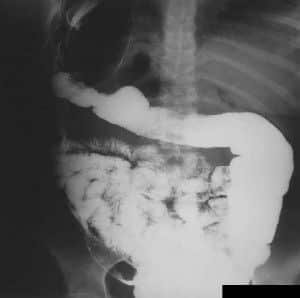

Abdomen, aparato digestivo y via biliarTécnicas de Exploración Radiológica Tránsito del intestino delgado Parte II 28 junio, 2012 Tidito Transito intestinal contraste simple Transito intestinal doble contraste yeyuno e ileon Patologia de Transito intestinal – Enfermedad celiaca Tumor maligno ileon terminalEnfermedad inflamatoria intestinal